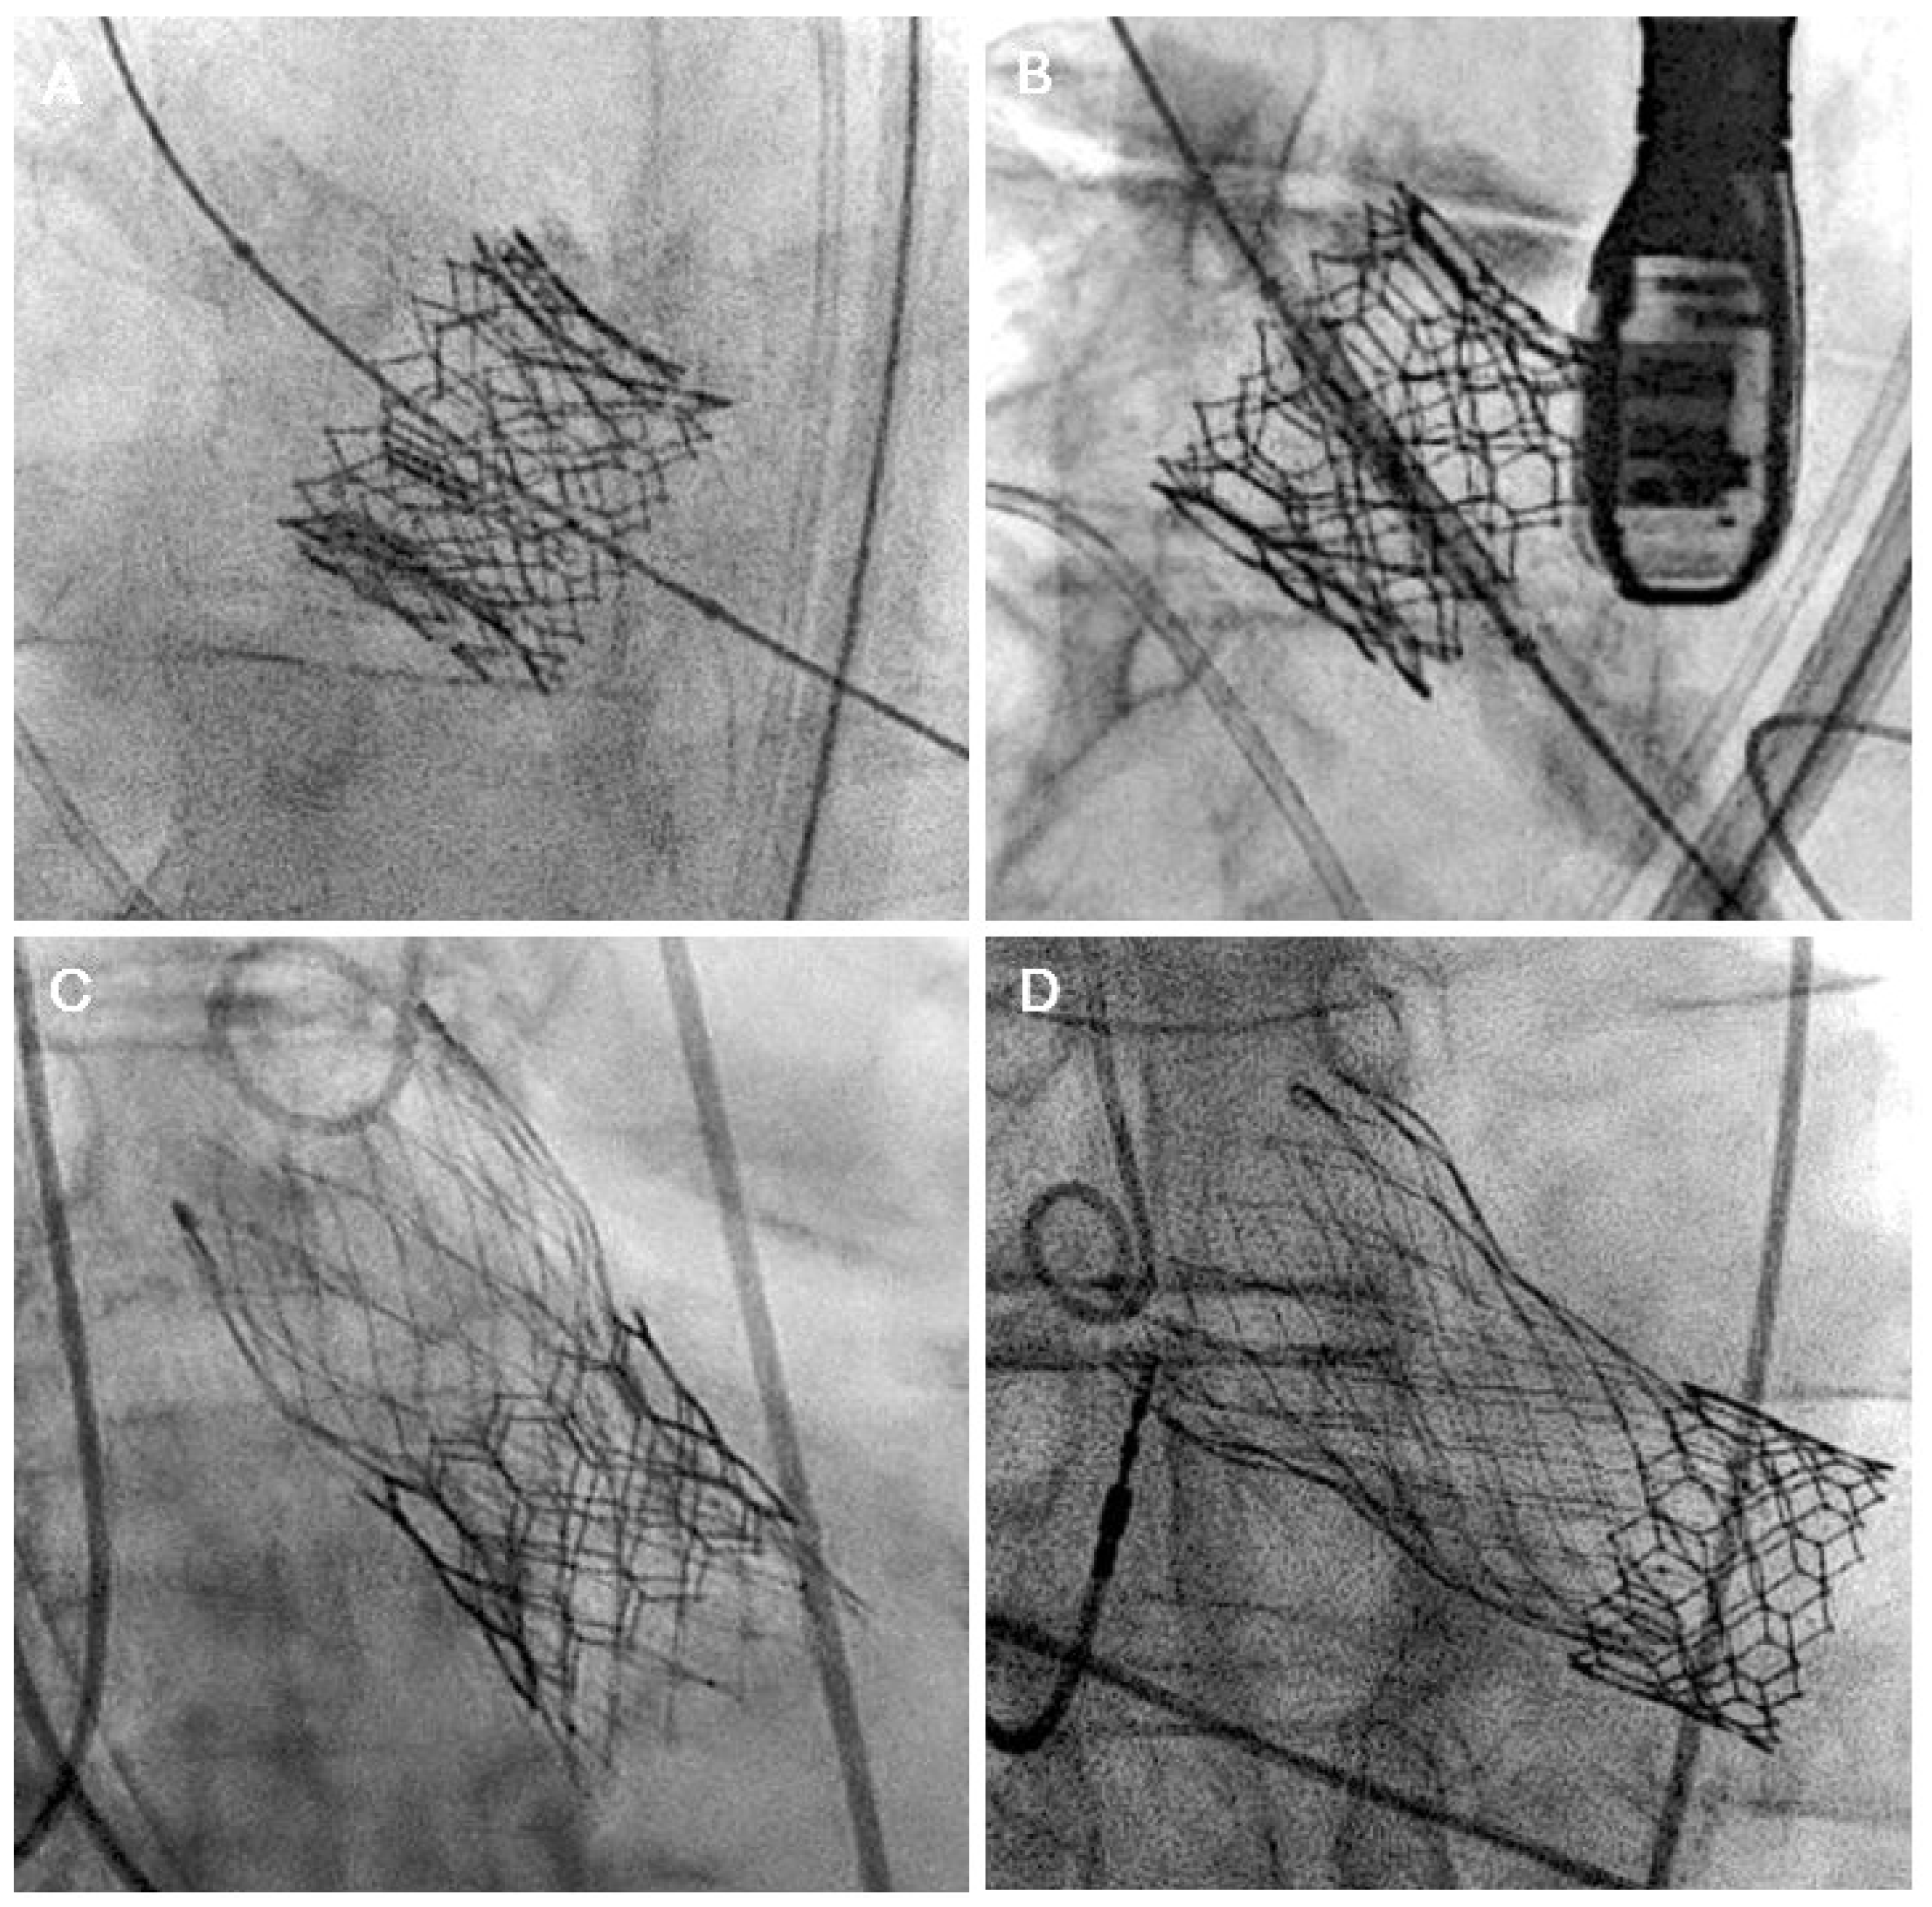

5.1. Coronary Occlusion Risk During Redo-TAVR and the Need for Protection

- Damlin, A.; Meduri, C.; Manouras, A.; Verouhis, D.; Linder, R.; Ruck, A.; Settergren, M. BASILICA Procedure Prior to Valve-in-Valve TAVR in a Supra-Annular TAV Prosthesis. JACC Case Rep. 2023, 11, 101777. [Google Scholar] [CrossRef]

- Dvir, D.; Leon, M.B.; Abdel-Wahab, M.; Unbehaun, A.; Kodali, S.; Tchetche, D.; Pibarot, P.; Leipsic, J.; Blanke, P.; Gerckens, U.; et al. First-in-Human Dedicated Leaflet Splitting Device for Prevention of Coronary Obstruction in Transcatheter Aortic Valve Replacement. JACC Cardiovasc. Interv. 2023, 16, 94–102. [Google Scholar] [CrossRef]

- Mew, C.; Dahiya, A.; Chong, A.A.; Hayman, S.M.; Moore, P.T.; Harrop, D.L.; Reyaldeen, R.; Cole, C.M.; Ross, J.D.; Roberts, S.; et al. First-in-human: Leaflet laceration with balloon mediated annihilation to prevent coronary obstruction with radiofrequency needle (LLAMACORN) for valve-in-valve transcatheter aortic valve replacement. Catheter. Cardiovasc. Interv. 2024, 104, 1079–1085. [Google Scholar] [CrossRef]